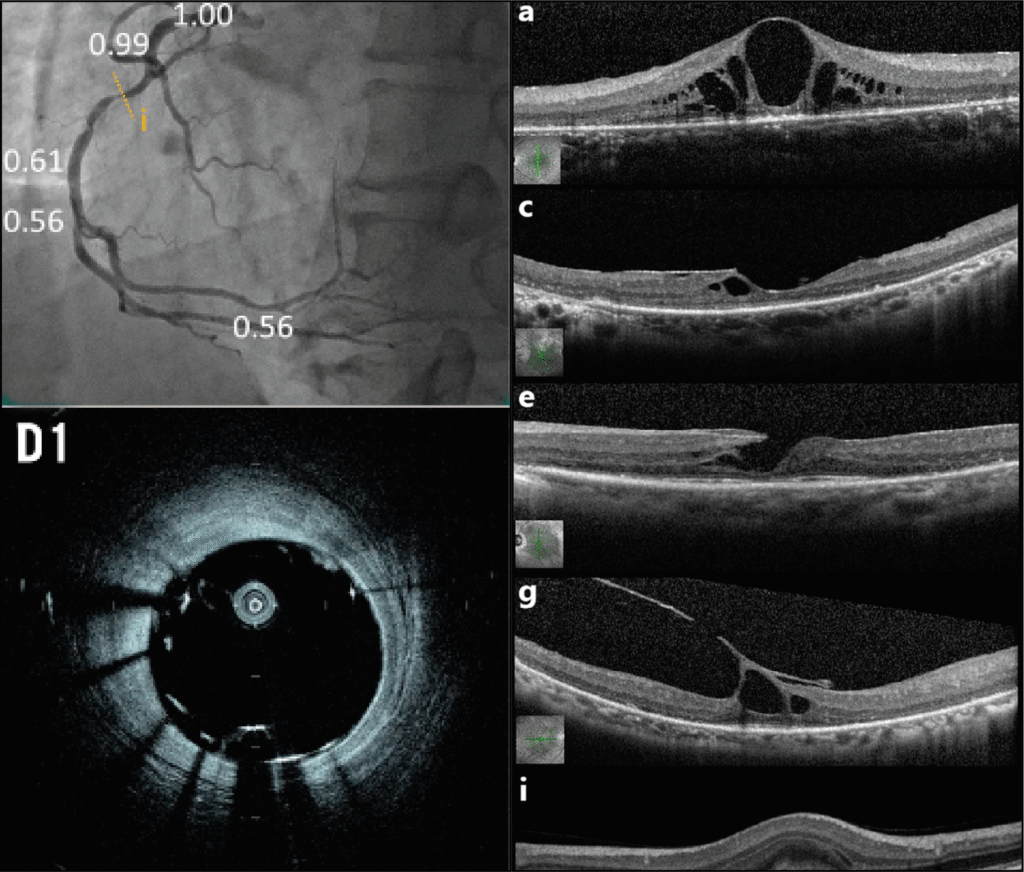

Imaging-Guided Interventions

(IVUS & OCT)

Dr. Grant has championed the use of intravascular imaging tools like IVUS (Intravascular Ultrasound) and OCT (Optical Coherence Tomography) to achieve precision-guided angioplasty results. These technologies ensure optimal stent placement and better long-term outcomes, marking a shift from conventional to precision-driven care.